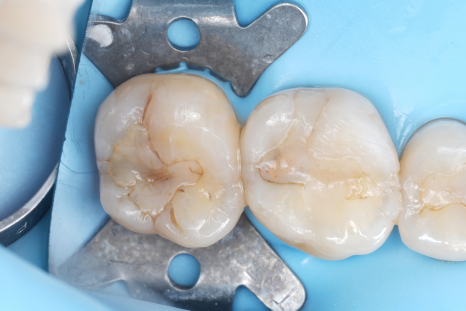

큐레이 전, 후

그럼에도 제가 큐레이를 고집하는 이유는 아주 단순해요. 충치와 건강한 치질의 경계를 정확하게 보여주기 때문입니다.

충치는 겉과 속이 다른 경우가 많아요.

치과보존과

겉으로 보기에는 작은 점처럼 보여도 안쪽에서는 더 넓게 진행되어 있는 경우도 꽤 많아요.

문제는 눈으로만 진료하면 이 경계를 정확히 판단하기 어렵다는 거예요.

그래서 치료를 하다 보면 이런 일이 생길 수 있어요. 충치가 아닌 부분까지 같이 삭제되거나 혹은 반대로 충치가 남아버리는 경우도 생기죠.

하지만 큐레이를 사용하면 충치가 있는 부분과 건강한 치질의 경계가 비교적 명확하게 드러나요. 말 그대로 '어디까지 진료해야 하는지'를 보여주는 장비라고 생각하시면 돼요^^